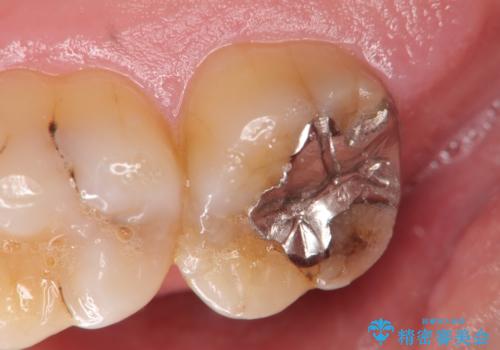

銀歯の劣化・セラミックインレー修復

- 以前に治療を行った銀歯がしみることの改善を希望して来院されました。

銀歯辺縁からのセメント漏洩が認められたため、セラミックインレーによる精度の高い修復を行うこととなりました。

辺縁の漏洩について

修復物の精度が悪いと、接着材であるセメントが漏出し痛みが生じることがあります。